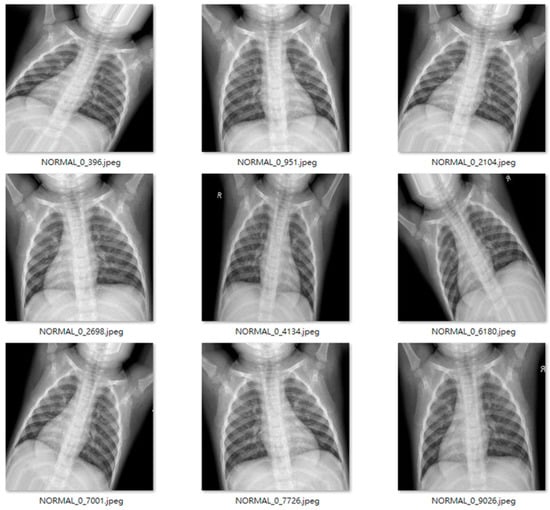

The study dataset included unbalanced positive and negative samples, with significantly fewer normal images than pneumonia images in both training and test sets and relatively low data volume. This could lead to poor post-training validation and overfitting. Therefore, we applied data augmentation on the original datasets, creating new images by horizontal flipping, rotating, scaling size and ratio, and changing brightness and color temperature for the original images to compensate for the lack of data volume. Data augmentation increased the training set from 5216 to 22,146 images, and the test set from 624 to 1000 images. Furthermore, some images were transferred from the training to test set for data balance and to ensure images in the test set were predominantly originals. Figure 11 and Figure 12 show examples of original and augmented images, respectively.

Figure 11. Example original images [31].